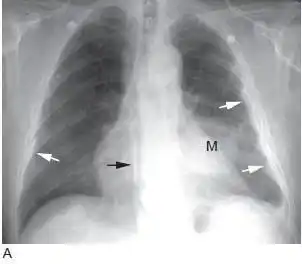

肺癌的影像学表现(上)(多图)